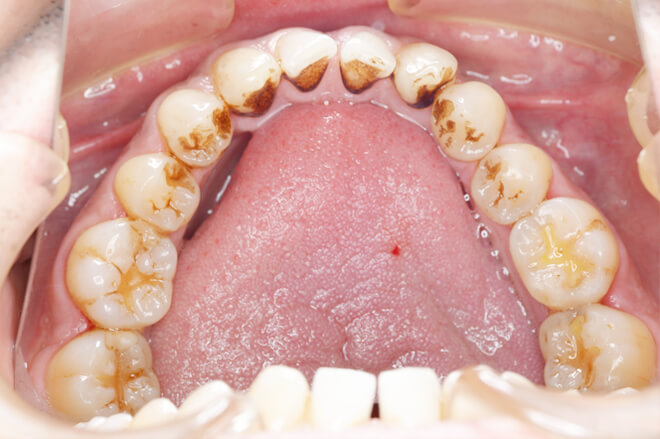

PMTC術前